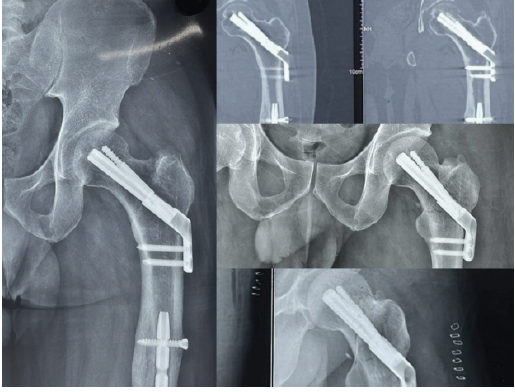

A 66-year-old female presented with a valgus-impacted Garden’s type I, Pauwel’s type I femoral neck fracture after a low-energy fall. Fixation was done in situ with the FNS device, applying mild compression and without any reduction maneuver. The blade and anti-rotation screw were positioned centrally with adequate tip-apex distance, and bi-cortical distal locking screws were used. By 3 months, radiographs showed complete bony union, and the patient returned to full function (Fig. 1). The good outcome could be attributed to the stable fracture pattern, early intervention, and favorable implant positioning.

Figure 1: Top left: pre-operative radiograph of Case 1; top center: immediate post-operative radiograph; top right: post-operative radiograph at 3 months. Bottom left – pre-operative AP radiograph of Case 2; bottom center – immediate post-operative radiograph; bottom right: post-operative radiographs at 3 months.

Case 2

A 64-year-old female sustained a valgus-impacted Garden’s type I, Pauwel’s type I fracture. Similar to the previous case, the fracture was fixed in situ with compression using the FNS device, with central implant placement and bi-cortical distal locking. At 3 months, complete union was observed, and functional recovery was achieved (Fig. 1). The predictable healing here may reflect the inherent stability of valgus-impacted fractures combined with timely fixation.